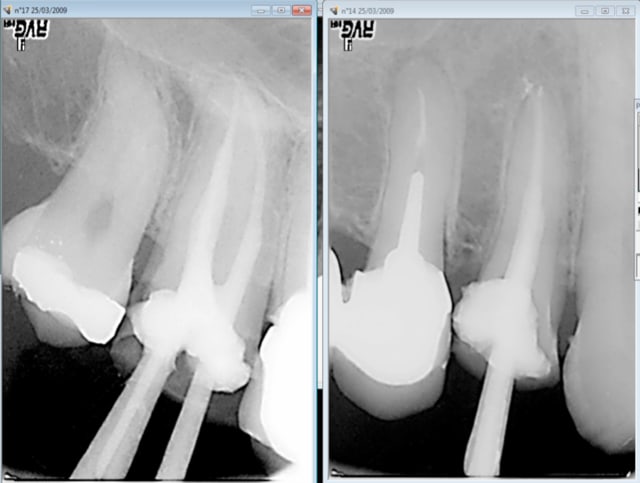

Comme celui ci cadre dans une grande entreprise avec une "bonne moutouelle" vu en urgence cette semaine suite à une bonne pèche sur 15-16 qui est reparti avec ca boite d'augmentin en attendant mieux. -)))

Capture d e cran 2016 04 08 12.08 - Eugenol

Capture d e cran 2016 04 08 12.09 - Eugenol

Capture d e cran 2016 04 08 12.23 - Eugenol

Enfin bon la 15 et la 16 je m'avance peut etre un peu. C'est possible que ce soit la 14 ou la 17 car en 2009 je ne mettais pas la digue et je ne condensais pas au mac spadden ( d'ailleurs ca c'est susceptible de constituer un indu car ca ne respecte pas les recommandations HAS lol !) . Qu'en pensez vous ? -))))